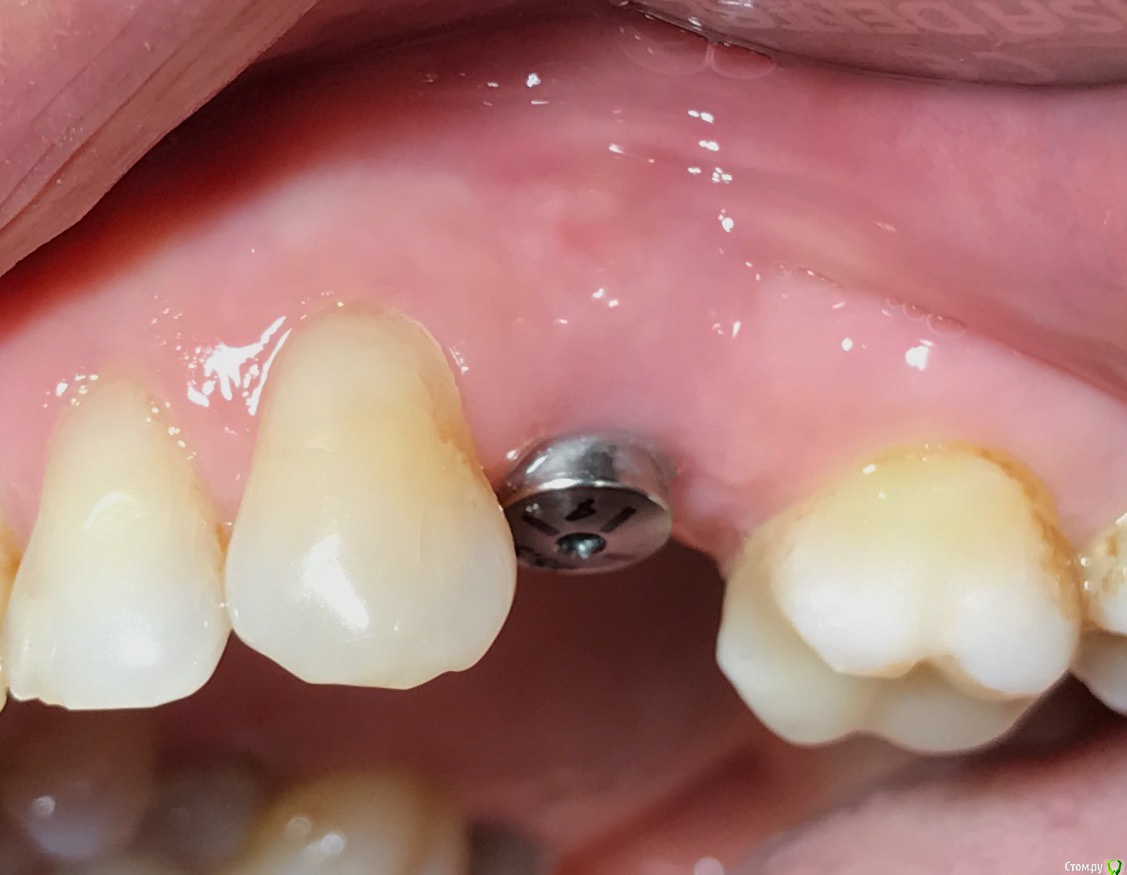

колесников Опубликовано 25 февраля, 2017 Поделиться Опубликовано 25 февраля, 2017 Здравствуйте коллеги! Представляю вашему вниманию этот клинический случай.В ноябре 2016 обратилась пациентка с жалобами на выпадение ортопедической конструкции в обл 24. Объективно: корни 24 не состоятельны. ,на десневом крае в проекции 24 свищевой ход с гнойным отделяемым.На КТ резорбция вестибулярной компактной пластинки и деструкция костной ткани в области щёчного корня.Приняв во внимание крайне негативное отношение пациентки к каким бы то ни было хирургическим вмешательствам и высоким эстетическим требованиям,было решено пойти на немедленную имплантацию .Снимки в день вмешательства,через 7,14 дней и 3мес.Имплант Astra tech profile 4.5х11мм. Сст с бугра вестибулярно. Вместо графта губки Коллапола (не вспомню причину,либо не было в наличии,либо отказ пациента). 15 Ссылка на комментарий

колесников Опубликовано 26 февраля, 2017 Автор Поделиться Опубликовано 26 февраля, 2017 Да,можно было ещё на 1мм притопить,и конечно графт вестибулярно оставить,но это стало понятно только сейчас. При постановке имплант был заглублен на 3 мм, посчитал что этого достаточно, но резорбция случилась больше планируемой. Первоначально планировалась нагрузка через 5 сут ,но ортопед позднее отказался от этой идеи. Думал заменить фдм на зебру,но пациентка пропала на 3 мес... Как получилось,так получилось. Торк был 35н/см,как обычно на астре. Ссылка на комментарий

колесников Опубликовано 12 июня, 2017 Автор Поделиться Опубликовано 12 июня, 2017 Контрольное кт спустя 3 мес. Откуда-то наросло 2мм у шейки. Ссылка на комментарий